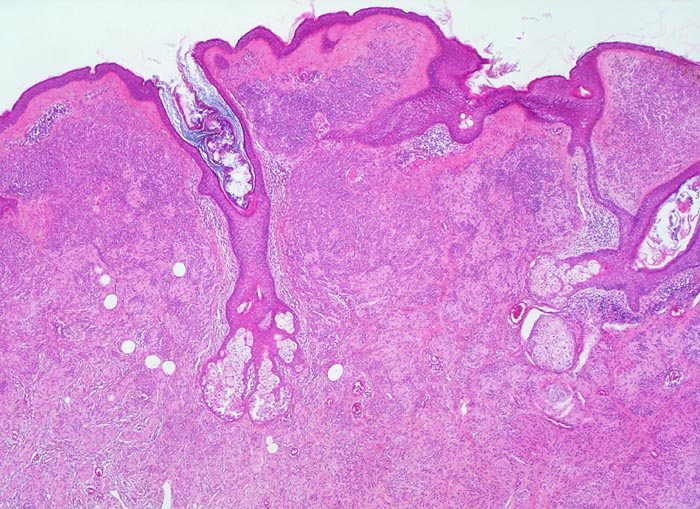

dermaler Naevuszellnaevus

benigner Tumor

Haut, Rumpf

Haut

Unauffällige Epidermis mit Haarfollikeln. Grosse konfluierende Nester von Naevuszellen füllen das Corium aus. Zwischen den Naevuszellen und der Epidermis schmale Schicht von zellarmem Bindegewebe (corialer=dermaler Naevuszellnaevus).

Graubraune, leicht erhabene, scharf begrenzte Hautveränderung über dem Schulterblatt.

Histologie

25